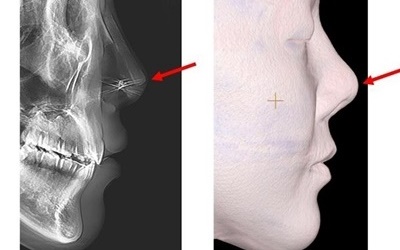

축농증의 진단은 신체 검사와 증상 검토를 통해 이루어지며, 영상 검사도 사용될 수 있습니다. 의사는 신체 검사 결과와 증상을 종합하여 진단을 내릴 수 있습니다. CT 스캔이나 비강 내시경 검사와 같은 영상 검사는 정확한 진단을 위해 도움을 줄 수 있습니다. CT 스캔은 부비동의 염증과 패혈증을 확인하는 데 사용되며, 내시경 검사는 부비동 내부를 시각화하여 염증 부위를 확인할 수 있습니다. 추가적으로, 증상의 지속과 재발 여부도 진단에 영향을 줄 수 있습니다.